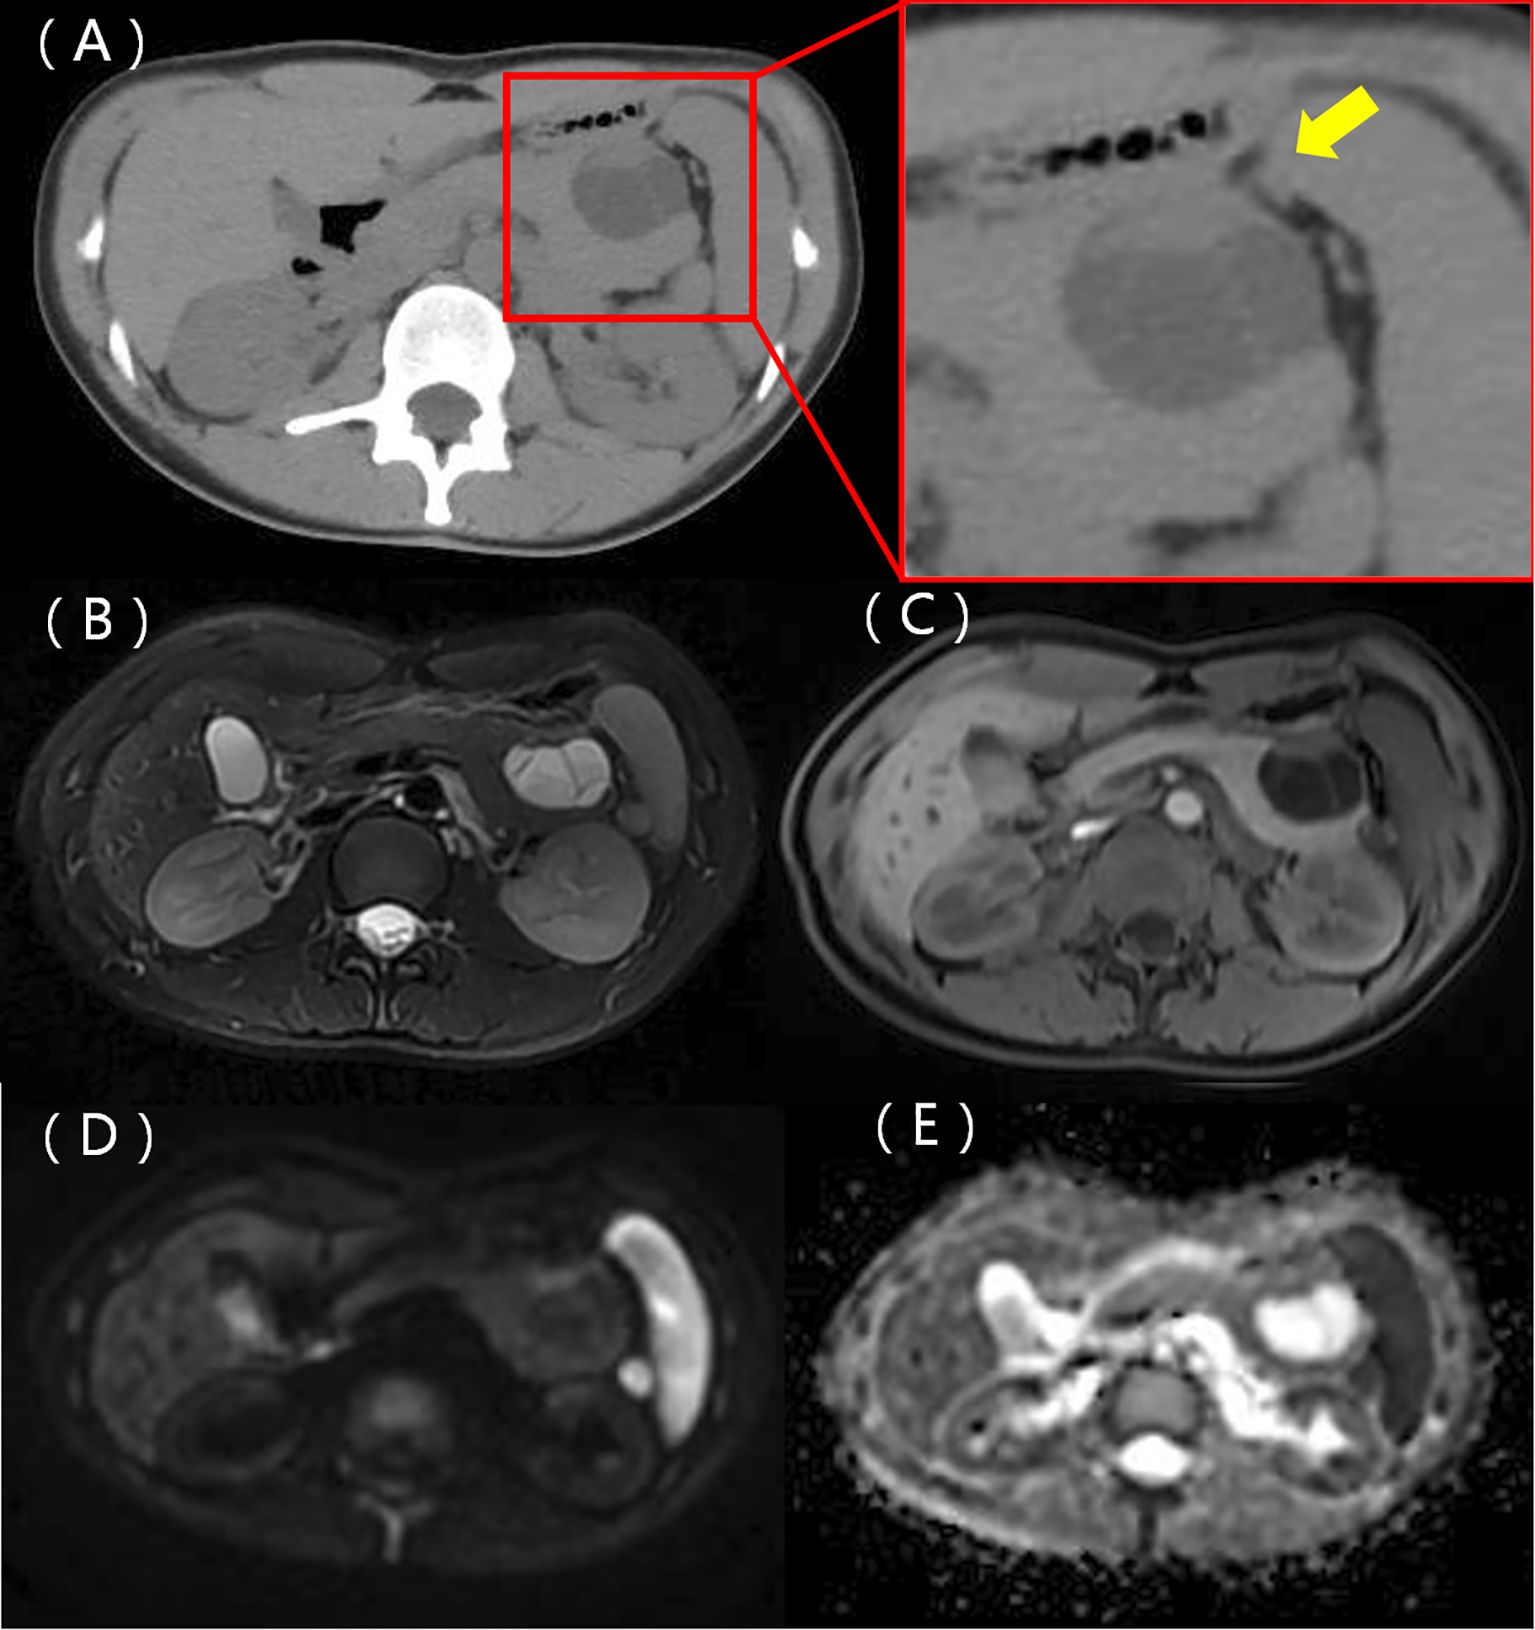

Figure 1

Ultrasound images showing two panels labeled A and B. Panel A displays a crosshair marker over an oval structure within the tissue. Panel B shows a similar structure with a cross and marker, indicating a measurement. Both images depict typical ultrasound gray-scale patterns.

Figure 1. Ultrasound showing a hypoechoic mass located in the body and tail of the pancreas with clear margins (A) and a nodule with strong echoes at the edge (B).

A 22-year-old woman was admitted to the hospital in August 2022 after a routine medical checkup revealed a cystic-solid mass in her pancreas. The patient’s past medical history, personal history, and family history were unremarkable. Physical examination of the abdomen revealed no notable findings. An ultrasound revealed a cystic mass in the tail of the pancreas with clear margins, multiple hyperechoic septa, and isoechoic nodules at the edge (Figure 1). Furthermore, a computed tomography (CT) plain scan revealed a cystic-solid mass in the body and tail of the pancreas, which appeared regularly shaped with solid components of equal density and septa (Figure 2A), measuring approximately 3.6 × 2.5 cm. There was no clear demarcation of the lesion from the adjacent organs and the peritoneum. To further assess the nature of the lesion, the patient underwent magnetic resonance imaging (MRI). The MRI findings revealed a cystic-solid mass in the body and tail of the pancreas with septa. The solid components and septations appeared isointense on the T1-weighted image (T1WI), while they were slightly hyperintense on the T2-weighted image (T2WI). The cystic components were hypointense on T1WI and hyperintense on T2WI (Figures 2B, C). The lesion was found to adhere tightly to the adjacent organs and the peritoneum. On diffusion-weighted imaging (DWI), the solid components displayed hyperintensity (b = 800 s/mm2) and hypointensity on the apparent diffusion coefficient (ADC) map (Figures 2D, E). Gadolinium-enhanced scanning revealed a slight enhancement of the solid components and septa in the arterial phase (Figure 3A), followed by continuous enhancement in the venous and delayed phases (Figures 3B, C). However, the cystic component did not display enhancement. The maximum intensity projection (MIP) image indicated an enlargement of the portal vein and tortuous dilation of blood vessels in the splenic hilum (Figure 3D). Moreover, Figures 3E, F display the preoperative three-dimensional MRI of the tumor and adjacent structures. The preoperative diagnosis was a solid pseudopapillary tumor of the pancreas.